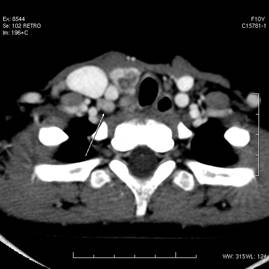

甲狀腺(拉丁語:Glandula thyr(e)oidea;英語:Thyroid)是脊椎動物非常重要的腺體,屬於內分泌器官。在哺乳動物它位於頸部甲狀軟骨下方,氣管兩旁。人類的甲狀腺形似蝴蝶,猶如盾甲,故名。

甲狀腺是人體最大的內分泌腺體,位於甲狀軟骨下緊貼在氣管第三,四軟骨環前面,由兩側葉和峽部組成,平均重量成大約20-25g,女性略大略重。甲狀腺後面有甲狀旁腺4枚及喉返神經。血液供應有上下左右四條動脈,所以甲狀腺血供較豐富,腺體受頸交感神經節的交感神經和迷走神經支配,甲狀腺的主要功能是合成甲狀腺激素,調節機體代謝,一般人每日食物中約有100-200μg 無機碘化合物,經胃腸道吸收入血循環,迅速為甲狀腺攝取濃縮,腺體中貯碘約為全身的1/5。碘化物進入細胞後,經過氧化酶的作用,產生活性碘迅速與膠質腔中的甲狀腺球蛋白分子上的酪氨酸基結合,形成一碘酪氨酸(MIT)和二碘酪氨酸(DIT),碘化酪氨

甲狀腺的被膜和毗鄰,甲狀腺有兩層被膜:氣管前筋膜包繞甲狀腺形成甲狀腺鞘,稱為甲狀腺假被膜;甲狀腺自身的外膜伸入腺實質內,將腺體分為若干小葉,即纖維囊,又稱甲狀腺真被膜。腺鞘與纖維囊之間的間隙內有疏鬆結締組織,血管,神經和甲狀旁腺等.手術分離甲狀腺時,應在此間隙內進行,並避免損傷不該損傷的結構。在甲狀腺左右葉的上端,假被膜增厚並連於甲狀軟骨,稱為甲狀腺懸韌帶;左右葉內側和甲狀腺峽後面的假被膜與環狀軟骨和氣管軟骨環的軟骨膜愈著,形成甲狀腺外側韌帶.上述韌帶將甲狀腺固定於喉及氣管壁上,因此,吞咽時甲狀腺可隨喉上,下移動,為判斷甲狀腺是否腫大的依據。喉返

甲狀腺前面由淺入深依次為皮膚,淺筋膜,頸筋膜淺層,舌骨下肌群和氣管前筋膜.甲狀腺葉的後內側與喉和氣管,咽和食管以及喉返神經等相毗鄰,其後外側與頸動脈鞘及鞘內的頸總動脈,頸內靜脈和迷走神經,以及位於椎前筋膜深面的頸交感乾相鄰。當甲狀腺腫大時,如向內側壓迫,可出現呼吸與吞咽困難和聲音嘶啞等,如向後外壓迫交感乾時,可出現HORNER綜合徵,即瞳孔縮小,上瞼下垂及眼球內陷等。